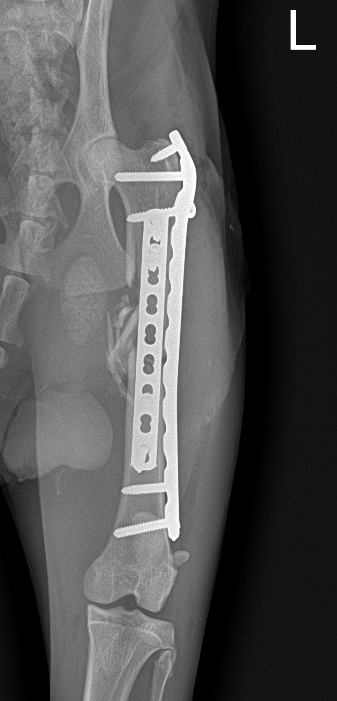

レントゲンを撮っていただくと、

「左大腿骨が折れている為、手術が必要」と診断いただきました。

【左側大腿骨骨幹部粉砕骨折】と診断されました。

術前レントゲン画像

画像の通り細かく骨が折れており、かなりの激痛だったと思います...